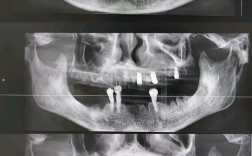

种牙后能否做CT是许多患者关心的问题,其实种植牙后进行CT检查不仅是可行的,在特定情况下还是必要的,种植牙作为一种精密的口腔修复方式,其成功与否与种植体周围骨组织、软组织的健康状况密切相关,而CT检查能提供清晰的影像学依据,帮助医生全面评估...